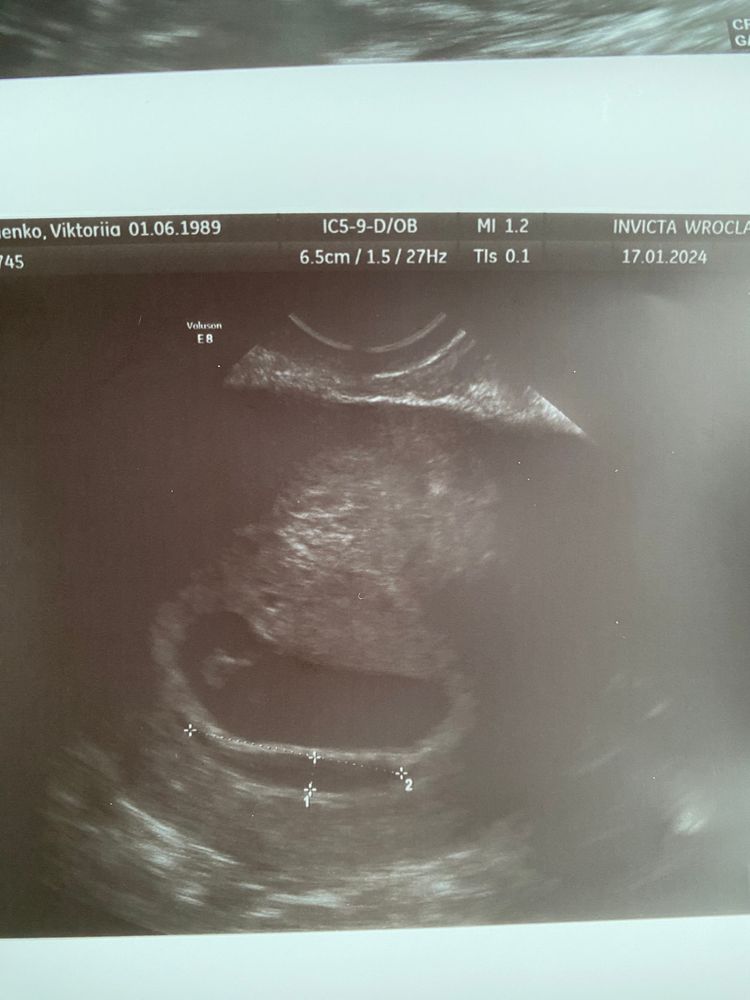

32 ДПП Новая гематома

Сохранение ЭКО-беременности

Сегодня пришла на контроль и вот тебе . Гематома по передней стенке 25 х 2мм. Прогестероновая поддержка хорошая, гормоны в норме. Откуда она вылезал не понятно.

эмбрион 1см, ❤️👍

От прошлой гематомы и следа не осталось (неделю назад вышла кровь и сгусток, на УЗИ обнаружили я так понимаю опорожнившуюся гематомы 7х4мм, кровоостанавливающие не назначали)